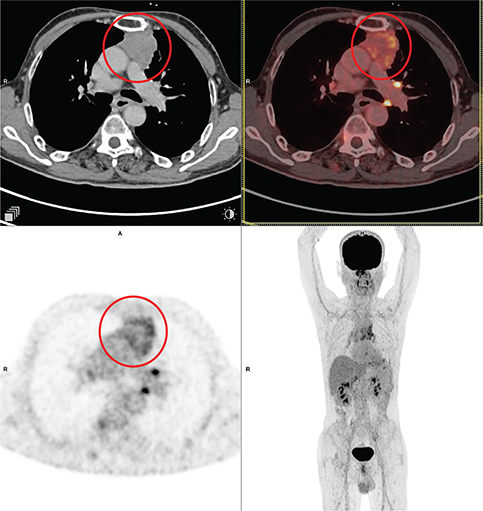

Fig 3

Figure 3. Seminoma. Anterior mediastinal mass that was pathologically confirmed as seminoma. FDG PET/CT images include axial CT (top left panel), fused axial PET/CT (top right panel), axial PET (bottom left panel), and maximum intensity projection (MIP) PET image (bottom right panel). In the red circle, a well-defined heterogeneously FDG avid and mildly enhancing lobulated soft tissue mass is seen in the anterior mediastinum on left side of midline. Non FDG avid non enhancing hypodense area seen within the mass representing necrotic component. The mass encases the arch of aorta.